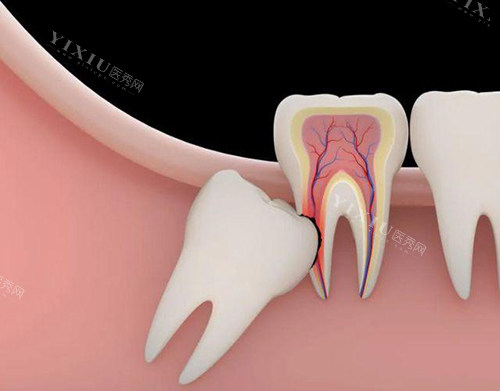

智齿疼痛的原因有很多。一方面,智齿生长受阻是常见原因。由于颌骨空间不足,智齿在生长过程中可能无法正常萌出,出现阻生情况。比如部分萌出的智齿,与周围牙齿间容易形成缝隙,食物残渣和细菌容易在此滞留,引发感染和炎症,导致疼痛。另一方面,智齿周围的牙周组织发炎,像智齿冠周炎,也会引起疼痛。还有可能是智齿出现了龋坏,导致牙髓炎等问题,进而引发疼痛。另外,智齿与邻牙的咬合关系不良,或者牙齿拥挤导致智齿位置不正,也会产生疼痛。

智齿反复疼痛可不能轻视,它会带来诸多危害。首先,智齿阻生可能会挤压邻牙,导致邻牙移位、扭转,影响正常的咬合关系,甚至可能引发颞下颌关节紊乱综合征。其次,智齿萌出不全容易形成盲袋,食物残渣堆积其中,滋生细菌,引发智齿冠周炎。炎症严峻时,可能会扩散到咀嚼肌间隙,导致张口受限、吞咽困难等症状。而且,智齿反复疼痛还会影响患者的日常生活,晚上疼起来会影响睡眠质量,第二天精神不振,影响工作和学习效率。

一般来说,如果智齿总是疼痛,很可能是因为发炎或者出现了阻生齿的情况,这种时候就需要考虑拔掉。比如智齿冠周炎患者,如果症状较轻,可以先在医生指导下使用过氧化氢溶液、复方氯己定含漱液等药物进行治疗;但如果症状较重,就需要拔掉智齿。牙髓炎患者,症状较轻时可使用甲硝唑、头孢他啶等药物进行抗感染治疗,症状严峻则需拔牙。龋病患者,症状较轻时可通过使用氟化亚锡、氟化铵等药物治疗,症状严峻也需要拔掉智齿。另外,如果智齿位置不正,与邻牙之间的咬合关系不良,导致牙齿过度磨损或创伤,或者智齿引起的问题无法通过其他方式解决,医生通常也会建议拔除智齿。